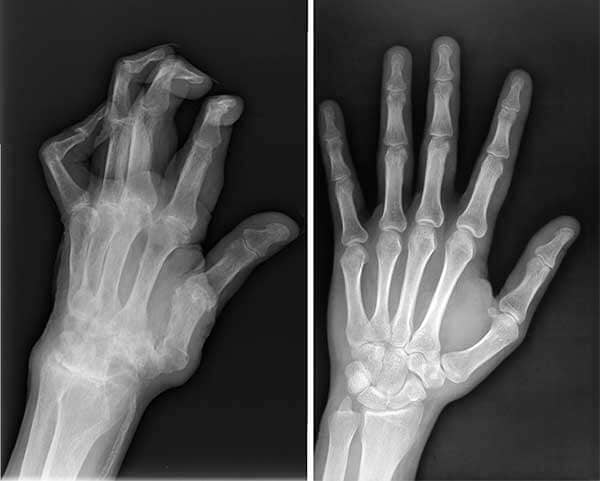

Manos antes y después

Radiografías de las manos de mi esposo antes y después de Sinoflex.